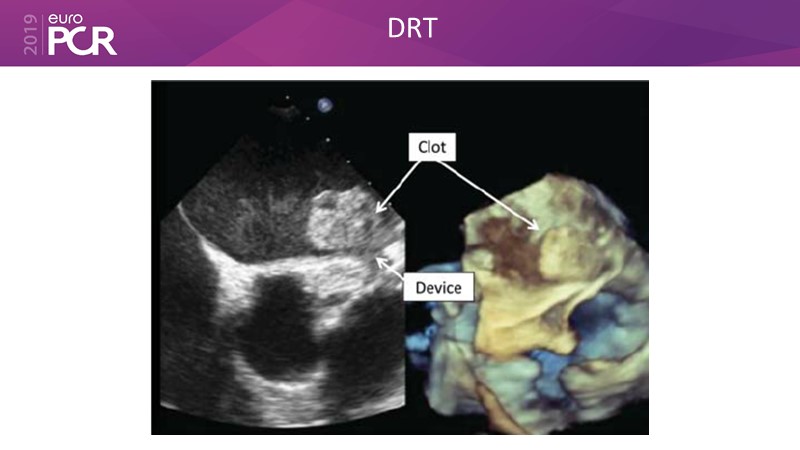

Post-procedural patient management

Previous Next